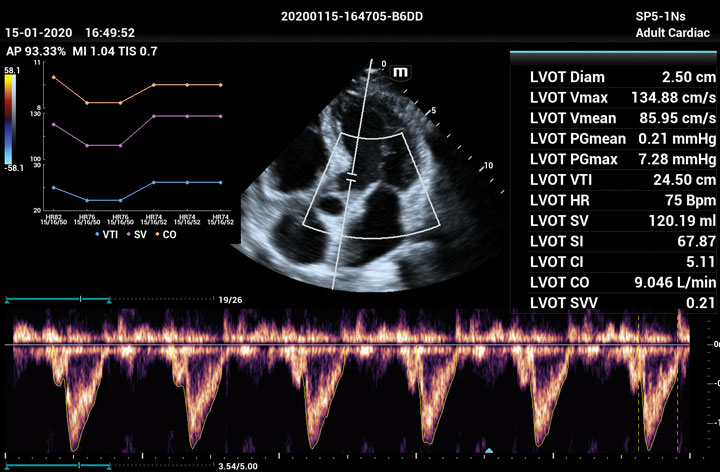

The ME8 Ultrasound System has been thoughtfully designed to overcome the obstacles clinicians face in today’s challenging healthcare environment. Powered by our groundbreaking software-based beamformer technology, ZONE Sonography® Technology+(ZST+), the ME8 Ultrasound System empowers decision-making by providing end-users best-in-class image quality and access to a comprehensive suite of workflow enhancement tools.